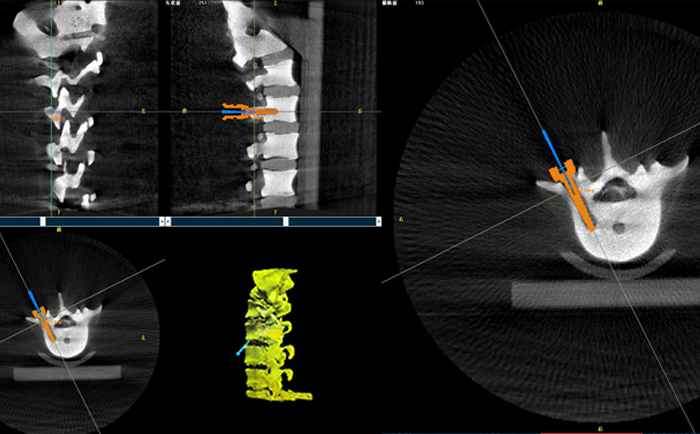

以椎弓根螺釘置入手術為例,傳統手術為了準確定位,需要將其多次進出反復選擇,增加了神經損傷與螺釘損壞的風險。但外科手術機器人可通過術前規劃把手術入路、方向、釘子深度都規劃好,基本做到一步到位,讓手術更加安全。

手術開始前,外科手術機器人與3D C形臂對患者的患處進行了一次掃描,做到“知己知彼”;接著電腦系統為每一顆螺釘設計出前進的路徑;隨后,“穩如泰山”的機器人之手——機械臂,開始為每條路徑掃除障礙,猶如鋪設火車軌道;最后沿標準路徑置入螺釘,猶如火車行駛在車軌之上,最終準確置入螺釘。

普愛醫療的外科手術機器人經國家藥監局批準,作為第三類醫療器械開始上市并應用于臨床,主要用于椎弓根螺釘內固定術、經皮穿刺椎體成形術等術式(包括頸椎、腰椎、胸椎等)等脊柱外科手術。輔助準確定位植入物或手術器械,精度達到亞毫米級,尤其對微創手術、高風險手術具有明顯優勢,可有效降低手術風險、減少手術并發癥。

PL300B骨科手術機器人搭配普愛醫療自主研發生產的3D C形臂(擁有獨立核心自主知識產權),借助一體化自適應配準技術,實現自動配準和注冊,通過預設參數以及智能算法,自動建立光學測位儀、患者和圖像三個坐標系關聯。系統兼容性更強,信息匹配更全面,配準過程更便捷、高效。